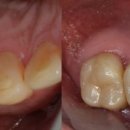

가장 정석적인 치료를 한다면 잇몸을 깨끗하게 관리하면서 교정을 하고 치아가 상실된 부위에 임플란트 또는 브릿지 치료를 하는 것입니다. 하지만 환자분께서는 교정치료를 하실 수 없는 상황이었고, 최소한의 보철로 최대한의 효과를 낼 수 있도록 치료 계획을 세웠습니다. 1. 먼저 심하게 흔들리는 앞니는 발치...

배태현 원장의 이보다 좋은 치과 이야기(2025-08-26 23:49:00)